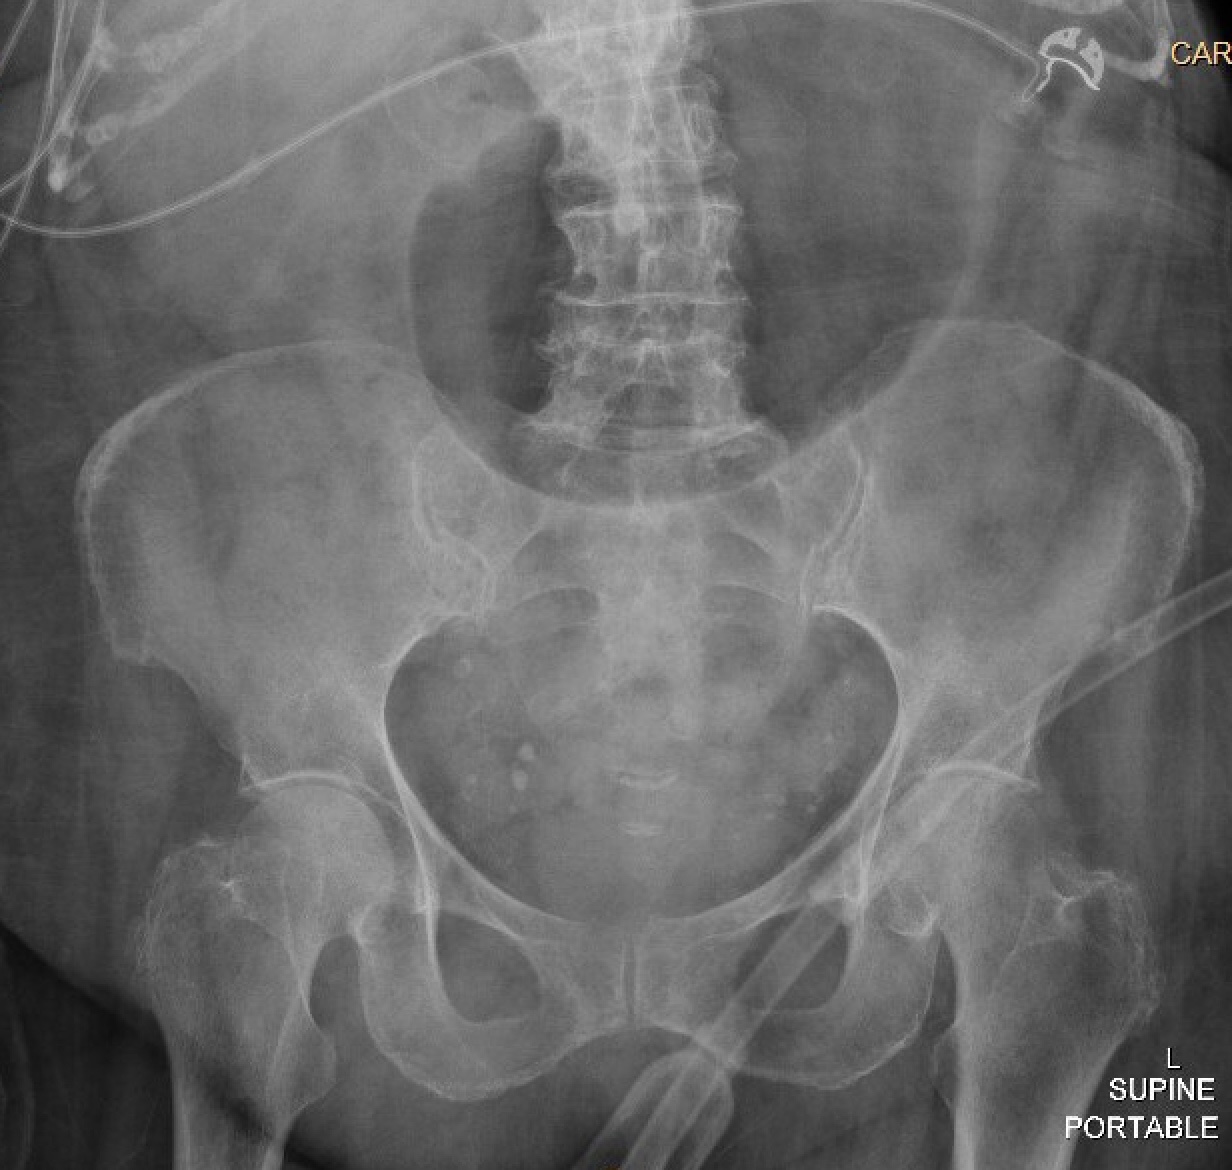

Case Presentation: An 84-year-old woman with type 2 diabetes mellitus, hypertension, prior ischemic stroke, osteoporosis, and rheumatoid arthritis presented to the hospital after a fall with altered mental status from increased home benzodiazepine use. During her admission, she developed acute nausea and vomiting with a new leukocytosis and was found to have acute cholecystitis. She underwent placement of a percutaneous cholecystostomy tube (PCT), completed intravenous antibiotics, and was discharged with the PCT in place. During her rehabilitation stay, her PCT was accidentally removed. She followed up with general surgery and was advised of the risk of gallstone complications, but given her frailty, the decision was made to allow for additional recovery prior to an elective cholecystectomy. Three months later, the patient presented to the emergency room with two days of abdominal pain, nausea, and vomiting. She had normal vital signs, and exam was notable for mild generalized abdominal tenderness, distention, and decreased bowel sounds. Laboratory evaluation revealed a white blood cell count of 21,100 cells/ul, a hemoglobin of 11.1 g/dL, normal sodium and chloride levels, a bicarbonate level of 36 mmol/L, blood urea nitrogen of 34 mg/dL, creatinine of 2.02 mg/dL (baseline is between 1.3 and 1.5 mg/dL). She had marked gaseous gastric distention on her initial abdominal x-ray. Subsequent computed tomography scan of the abdomen showed interval fistulization of the gallbladder and the gastric antrum/first portion of the duodenum with multiple gallstones extending through the fistula into the stomach and duodenum, resulting in gastric outlet obstruction, known as Bouveret syndrome. A nasogastric tube was placed for gastric decompression, and she underwent esophagogastroduodenoscopy for lithotripsy and removal of the gallstones. Attempted removal of the stones led to an esophageal tear. An esophageal stent was placed, but the patient developed bilateral empyemas requiring chest tube placement. She had a prolonged hospital course during which she was intubated and required enteral feedings through a nasojejunal tube.